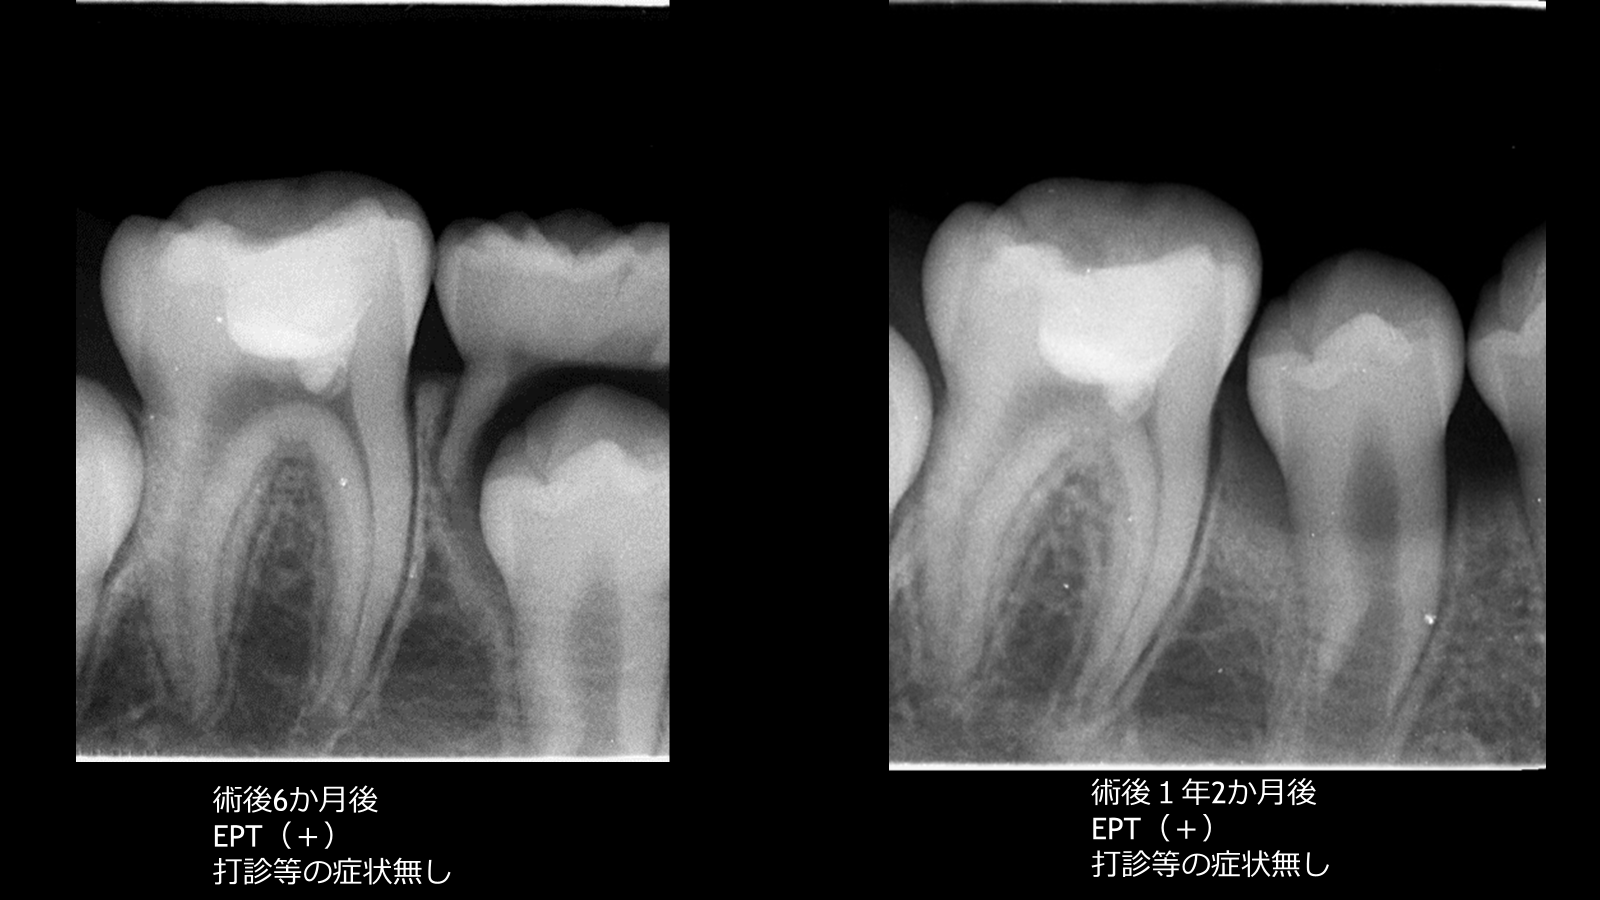

術後は定期的に経過観察を行い、

6か月後および約1年後のレントゲンにて

症状なし

EPT(+)

歯根の成長を確認

歯髄の生活反応および歯根発育を認め、良好な経過を示している。